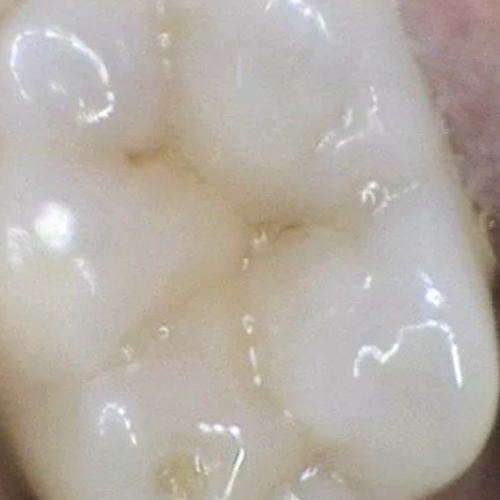

Dental Sealants are thin plastic coatings that are applied to the chewing surfaces of the back teeth (premolars and molars) to help protect them from decay.

The back teeth have pits and grooves on their chewing surfaces that are difficult to clean, making them more susceptible to decay.